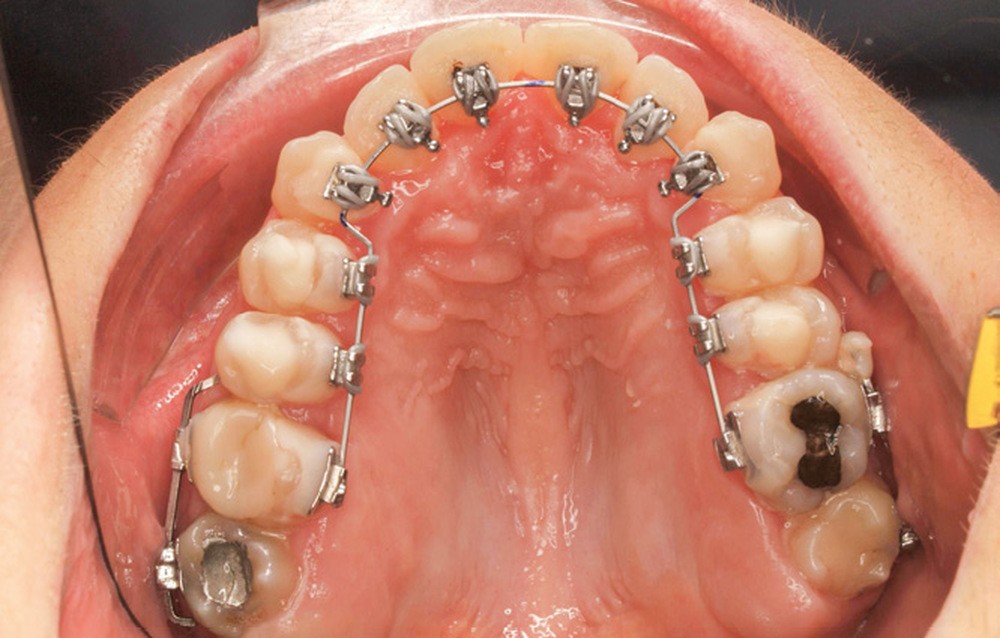

Le traitement est effectué avec un appareil lingual bimaxillaire et des attaches en .018 x .025 à insertion horizontale. L’appareil est réalisé intégralement au cabinet à partir d’un set-up conçu selon les objectifs décrits.

- Premier rendez-vous (fig. 2a) : l’arcade maxillaire est appareillée et un arc NiTi .014 en expansion est placé. L’arcade mandibulaire reçoit des cales rétro-incisives pour lever l’occlusion inversée. Par confort, des cales prémolaires, sans contact avec les dents antagonistes, sont posées pour réduire l’inocclusion latérale.

- Deuxième rendez-vous (fig. 2b) : les dents restantes sont collées et le même arc NiTi .014 est maintenu. Les cales rétro-incisives sont déposées et l’arcade mandibulaire est collée, un arc NiTi 0.014 posé.

- Troisième rendez-vous (fig. 2c) : les arcs NiTi .014 sont religaturés pour améliorer le nivellement-alignement.

- Quatrième rendez-vous (fig. 2d) : des arcs TMA .017 x .017 sont posés. Les premières et deuxièmes molaires sont collées en vestibulaire avec un arc sectionnel NiTi 0,019×0,025.

- Cinquième rendez-vous (fig. 2e) : des arcs TMA .017 x .025 sont posés et des tubes linguaux collés sur 17 et 27 pour le port d’élastiques criss-cross nocturnes.

- Sixième rendez-vous (fig. 2f) : les cales sont déposées. Un pliage de finition sur 21 est réalisé pour améliorer son angulation.